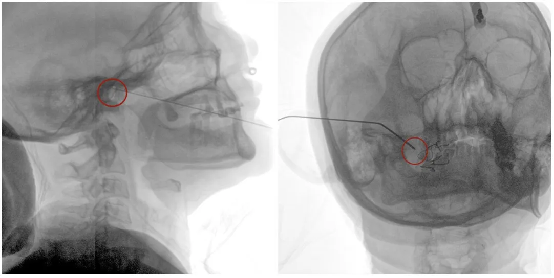

In the minimally invasive interventional treatment of trigeminal neuralgia, radiofrequency thermocoagulation has become one of the most widely used clinical techniques due to its simple procedure, reliable therapeutic efficacy, and the feasibility of repeat treatment in cases of recurrence. Common puncture approaches include the Hartel anterior approach, the submandibular–foramen ovale approach, and the lateral approach. Through these routes, high-frequency electrical current is delivered via an electrode to selectively ablate the pain-transmitting sensory fibers within the trigeminal ganglion, while preserving motor fibers and tactile sensory fibers.

The foramen ovale is an oval-shaped opening located in the greater wing of the sphenoid bone at the skull base, with a diameter of only 3–5 mm. It serves as a critical passage for the mandibular branch of the trigeminal nerve, the lesser petrosal nerve, and related vasculature, and is also the only “gateway” through which a radiofrequency electrode can percutaneously access the intracranial trigeminal ganglion.

Due to its deep anatomical location and significant inter-individual variability, even a minor deviation in trajectory can result in failure to cannulate the target neural structure or, more critically, misplacement into adjacent vital tissues. Therefore, precise localization of the foramen ovale represents the most critical challenge of the procedure. Accurate targeting can reduce the number of puncture attempts, shorten operative time, and lower both intraoperative patient discomfort and radiation exposure. Moreover, precise localization helps preserve normal nerve function to the greatest extent, reducing the incidence of postoperative complications such as facial numbness (hypesthesia) or dysesthesia, thereby improving patients’ quality of life and lowering the recurrence rate.

Based on the 3D images, the doctor plans the optimal puncture path to ensure precise alignment between the puncture direction and the foramen ovale, minimizing puncture deviations.

Electrical Stimulation Test

After the puncture needle reaches the target area, it is connected to a radiofrequency generator for electrical stimulation testing, while the patient’s facial responses are observed to confirm the precise positioning of the electrode tip at the root of the specific trigeminal branch responsible for the pain. Once positioning is completed, anesthetic and sedative drugs are administered intravenously to induce a controlled sleep state in the patient, followed by radiofrequency ablation. After the radiofrequency ablation treatment, the patient is allowed to awaken, the puncture wound is dressed with an adhesive bandage, and the surgery is completed.